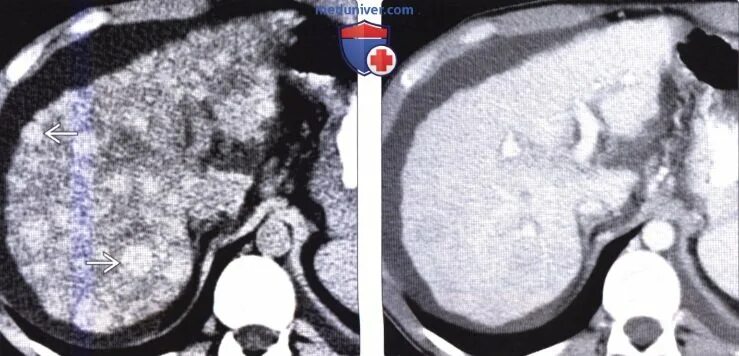

Цирроз на кт